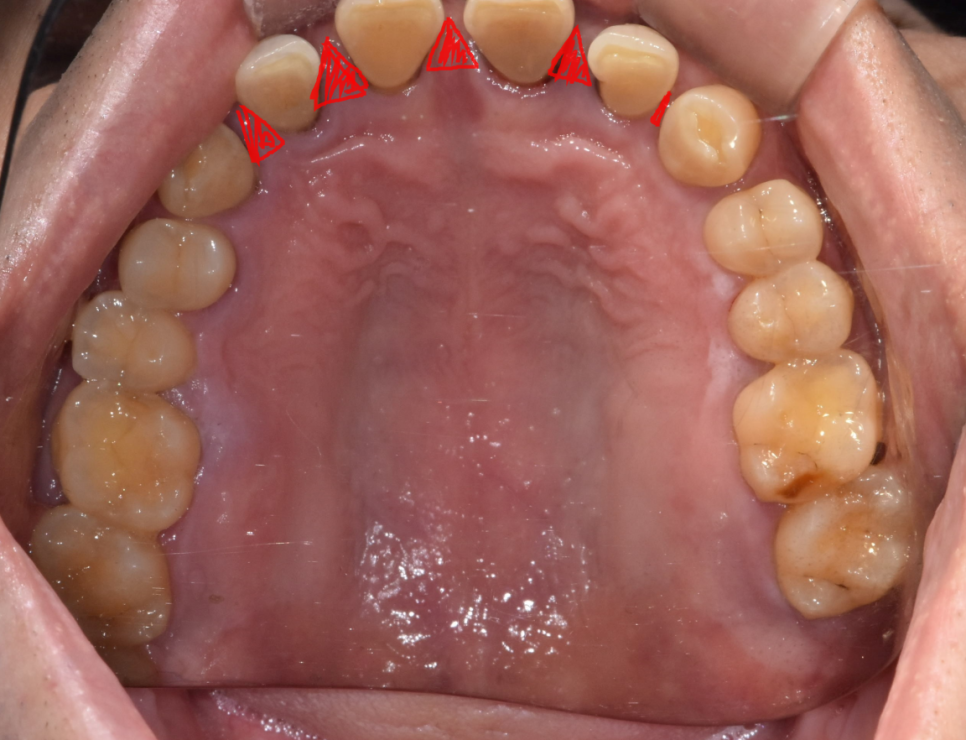

오늘 환자분은 위아래 앞니 모두 사이 사이 공간이 있었습니다.

벌어진 공간이 꽤 컸기 때문에

레진이나 라미네이트로는 한계가 있었습니다.

치아 사이즈가 더 커져서

비슷한 크기로 조화롭게 치료하기 위해서는

앞니를 크라운 치료를 통해 벌어진 것을 메꾸기로 했습니다.